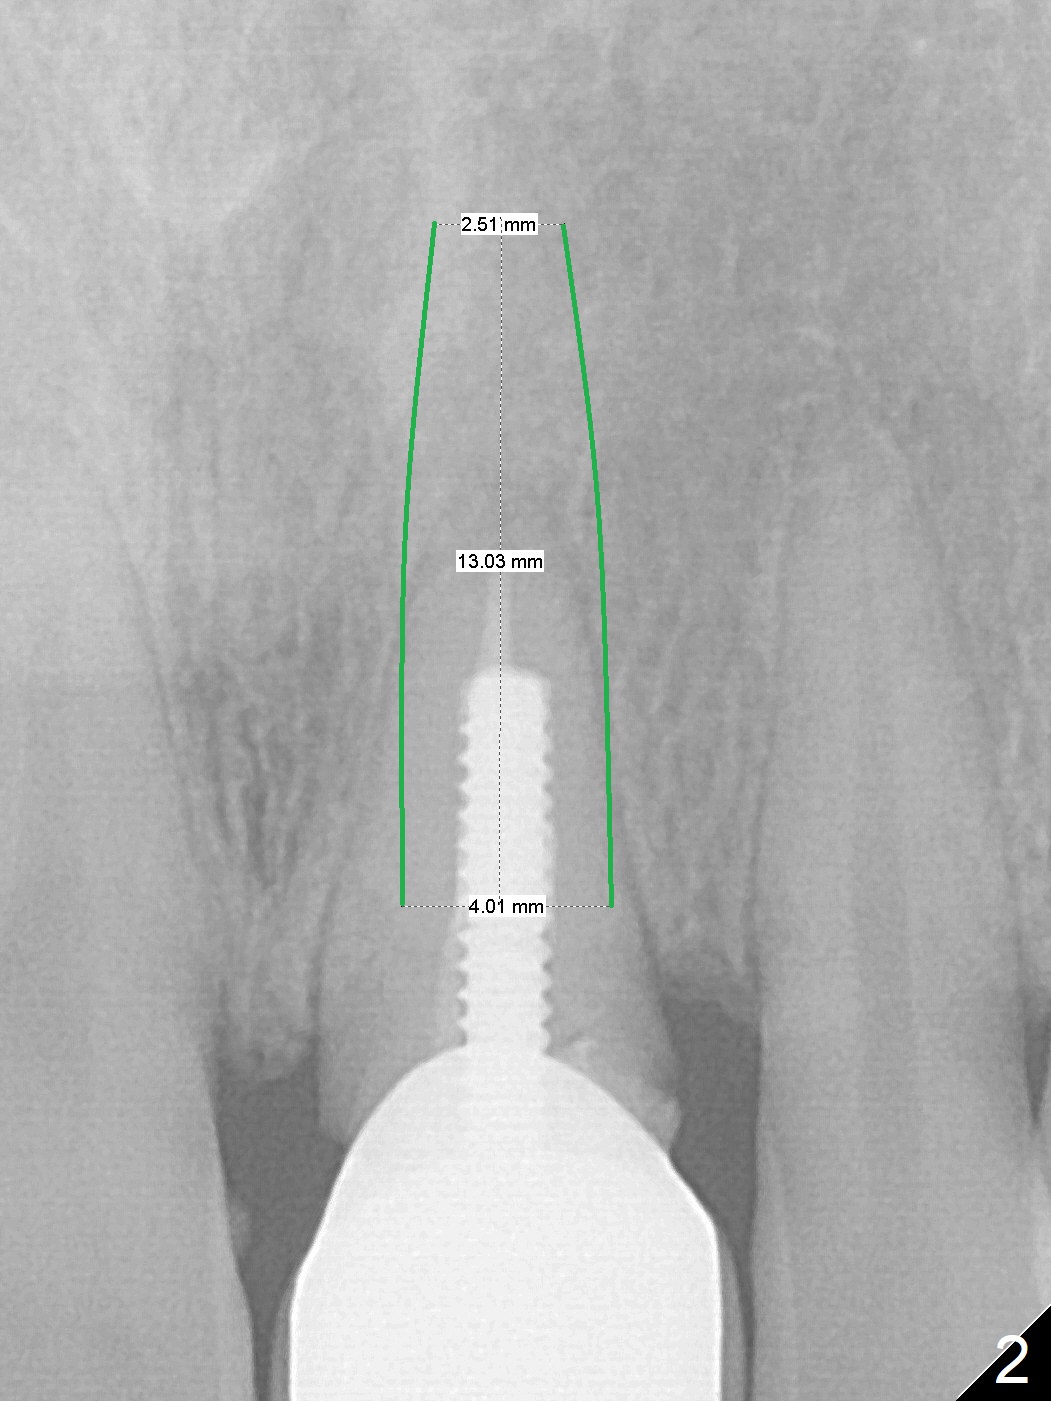

Non-Gold Coated Abutment

A 35-year-old woman's #9 fractures (Fig.1) because of blow by her child's head. Since a non-gold coated abutment will be used, an implant should be placed as palatal as possible (Fig.2). If the trajectory of the osteotomy turns out to be unacceptable, switch the other implant system with gold coated abutment. Perform socket shield, if extraction is difficult.